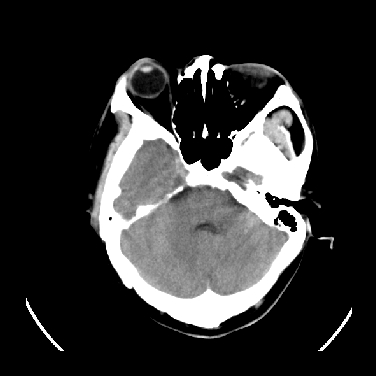

标题: CT16999:男,45岁,左侧肢体乏力1周。请会诊 [打印本页]

男,45岁,左侧肢体乏力1周。ex:胸片示:两肺团块状、斑片状密度增高影,其内可见小空洞。支纤镜、经皮肺穿示:干酪样物。

结合病史考虑结核性脑炎脑膜炎,伴脑脓肿形成

考虑结核性脑炎脑膜炎,伴脑脓肿形成。